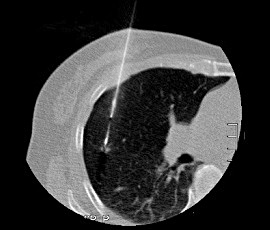

CTガイド下針生検